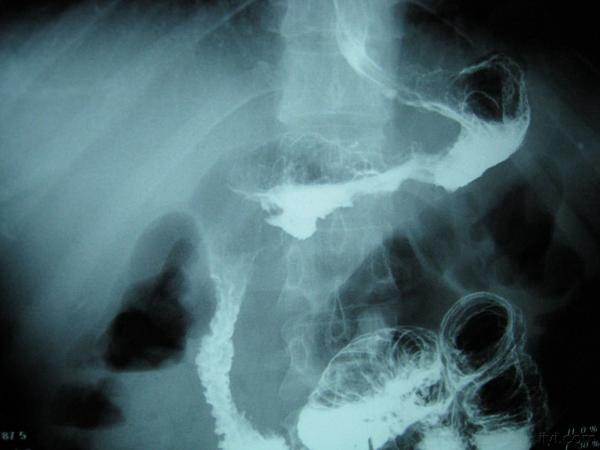

典型皮革胃!!!!

刚收一典型的皮革胃,准备明天腔镜下全胃切除,这个造影做的不错,希望对大家有帮助,只是照的不太好,见谅!!!

简单介绍一下皮革胃 皮革胃可以说是胃癌的一种,生长方式主要还是浸润式生长,最后使胃失去功能,使胃缩小,质地硬,像皮革一样,有称呼为革囊胃 临床上表现 1症状早期表现为上腹不适 2晚期可以摸到胃部 隆起 3贫血、消瘦、腹水等等!~ 检查: X线检查,造影 纤维胃镜, CT 细胞脱落病理检查 治疗: 手术行胃Ca 根治术 化疗 肠道营养 说的不太详细,以书本为主吧